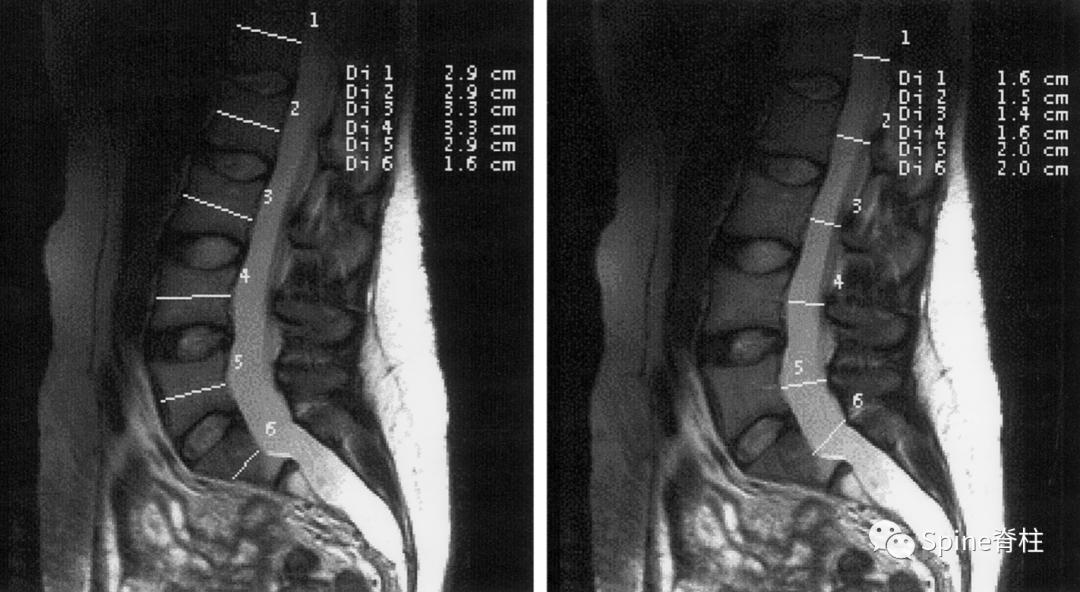

正中矢状位所示中断椎体直径测量(左图)和硬膜囊直径的测量(右图)。L1-S1的硬膜囊比的临界值(cutoff values)分别为0.64、0.55、0.47、0.48、0.48和0.57。利用L3或S1的临界值,诊断硬膜扩张的敏感性为95%,特异性为98%。